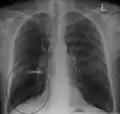

A chest X-ray is not useful to establish a diagnosis of COPD but it is of use in either excluding other conditions or including comorbidities such as pulmonary fibrosis, and bronchiectasis. Characteristic signs of COPD on X-ray include hyperinflation (shown by a flattened diaphragm and an increased retrosternal air space) and lung hyperlucency.[5] A saber-sheath trachea may also be shown that is indicative of COPD.[104]

Chest X-ray demonstrating severe COPD: Note the small heart size in comparison to the lungs.